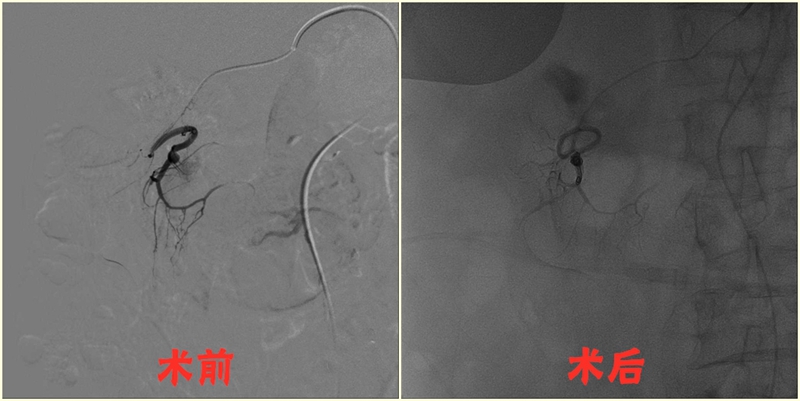

1.急性脑栓塞大血管取栓术:

先后开展大脑中动脉、大脑前动脉、颈内动脉、基底动脉急性闭塞机械取栓术。

2.脑动脉瘤栓塞术:

开展前交通动脉瘤、后交通动脉瘤、脉络膜前动脉瘤、大脑中动脉瘤、基底动脉瘤栓塞术。